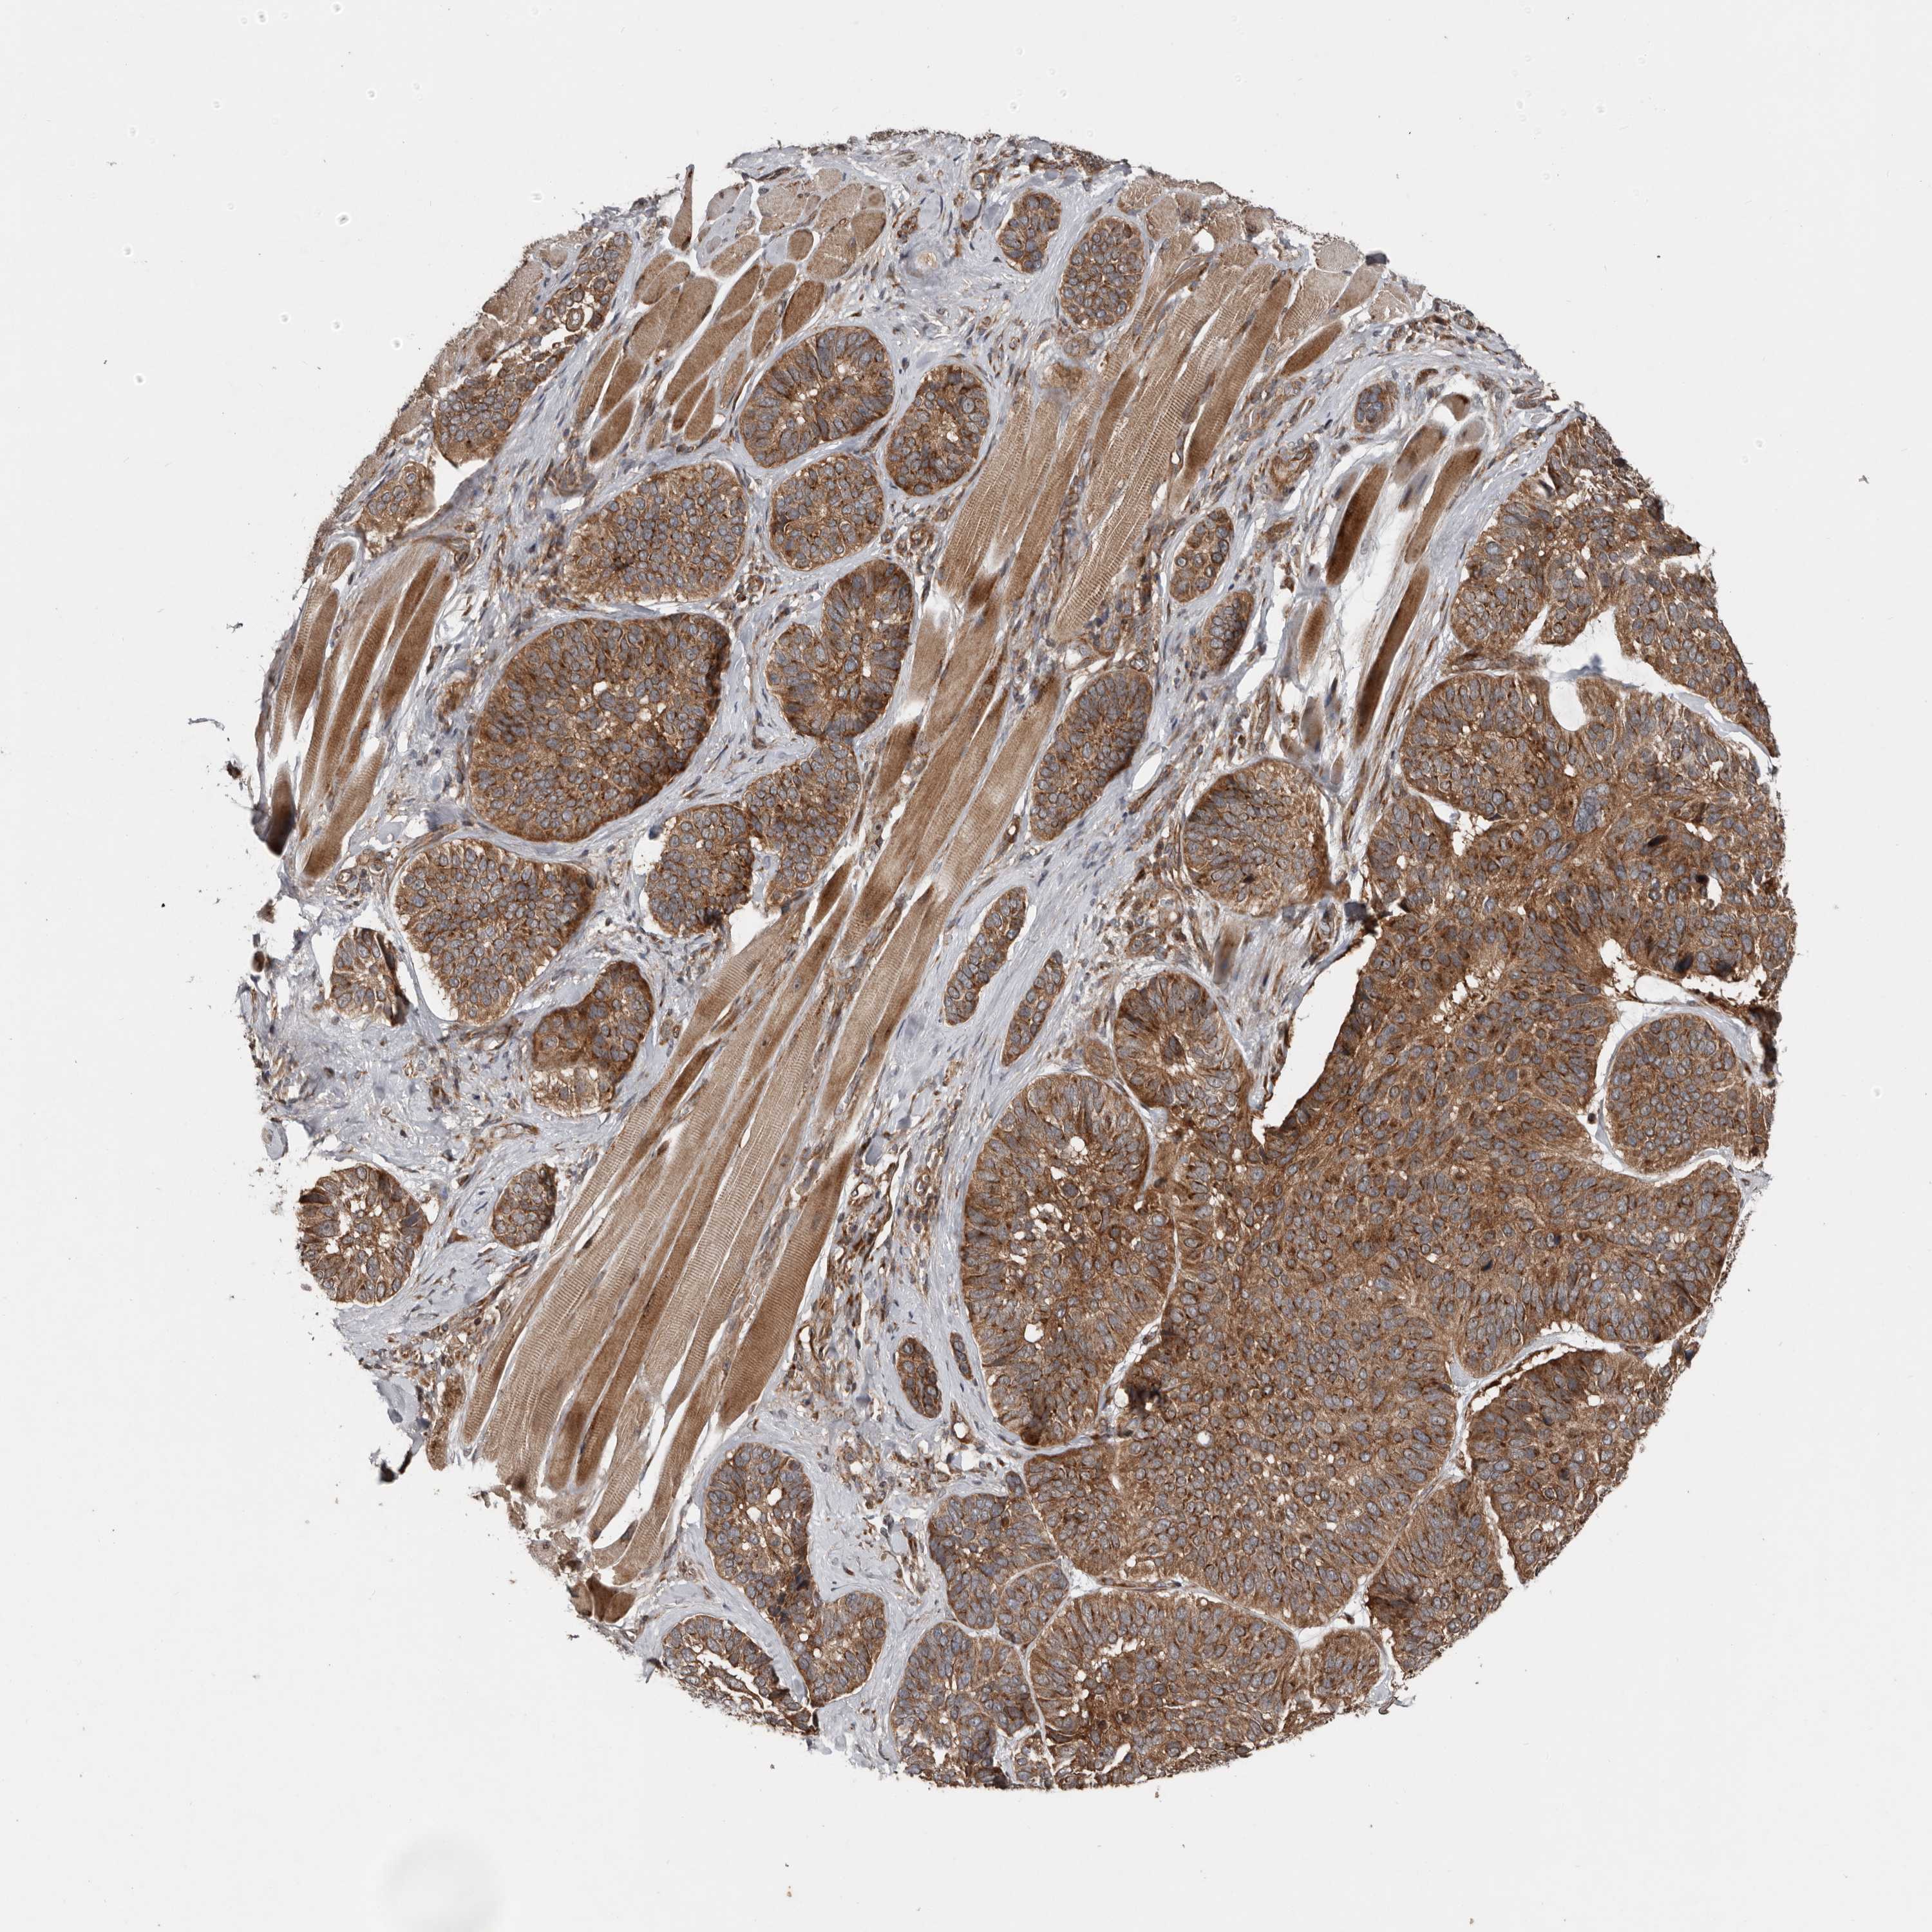

SKIN CANCER - Protein expressioni

A mouse-over function shows sample information and annotation data. Click on an image to view it in a full screen mode. Samples can be filtered based on level of antibody staining by selecting one or several of the following categories: high, medium, low and not detected. The assay and annotation is described here.

Each image is clickable and will lead to virtual microscopy that enables deeper exploration of all samples and also displays staining intensity scores, fraction scores and subcellular localization as well as patient and tissue information for each sample.

Antibody HPA028584

Squamous cell carcinoma, NOS